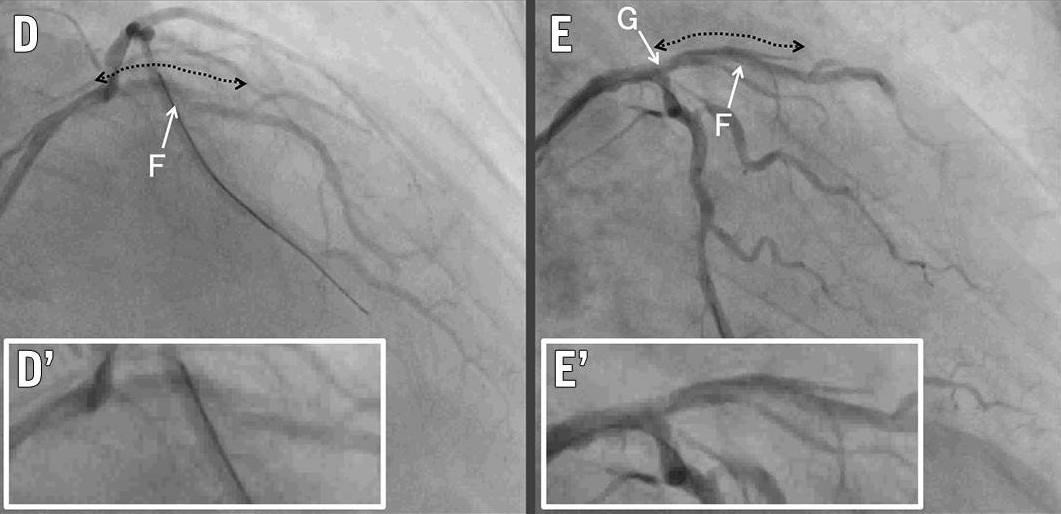

紧急冠脉造影(图1D-E,视频1、视频2):

LAD血流下降至TIMI 2级

夹层范围:LAD开口延伸至LAD近段

D-E. 夹层发生:LAD夹层(虚线箭头),TIMI 2级血流,(D'、E')放大图像